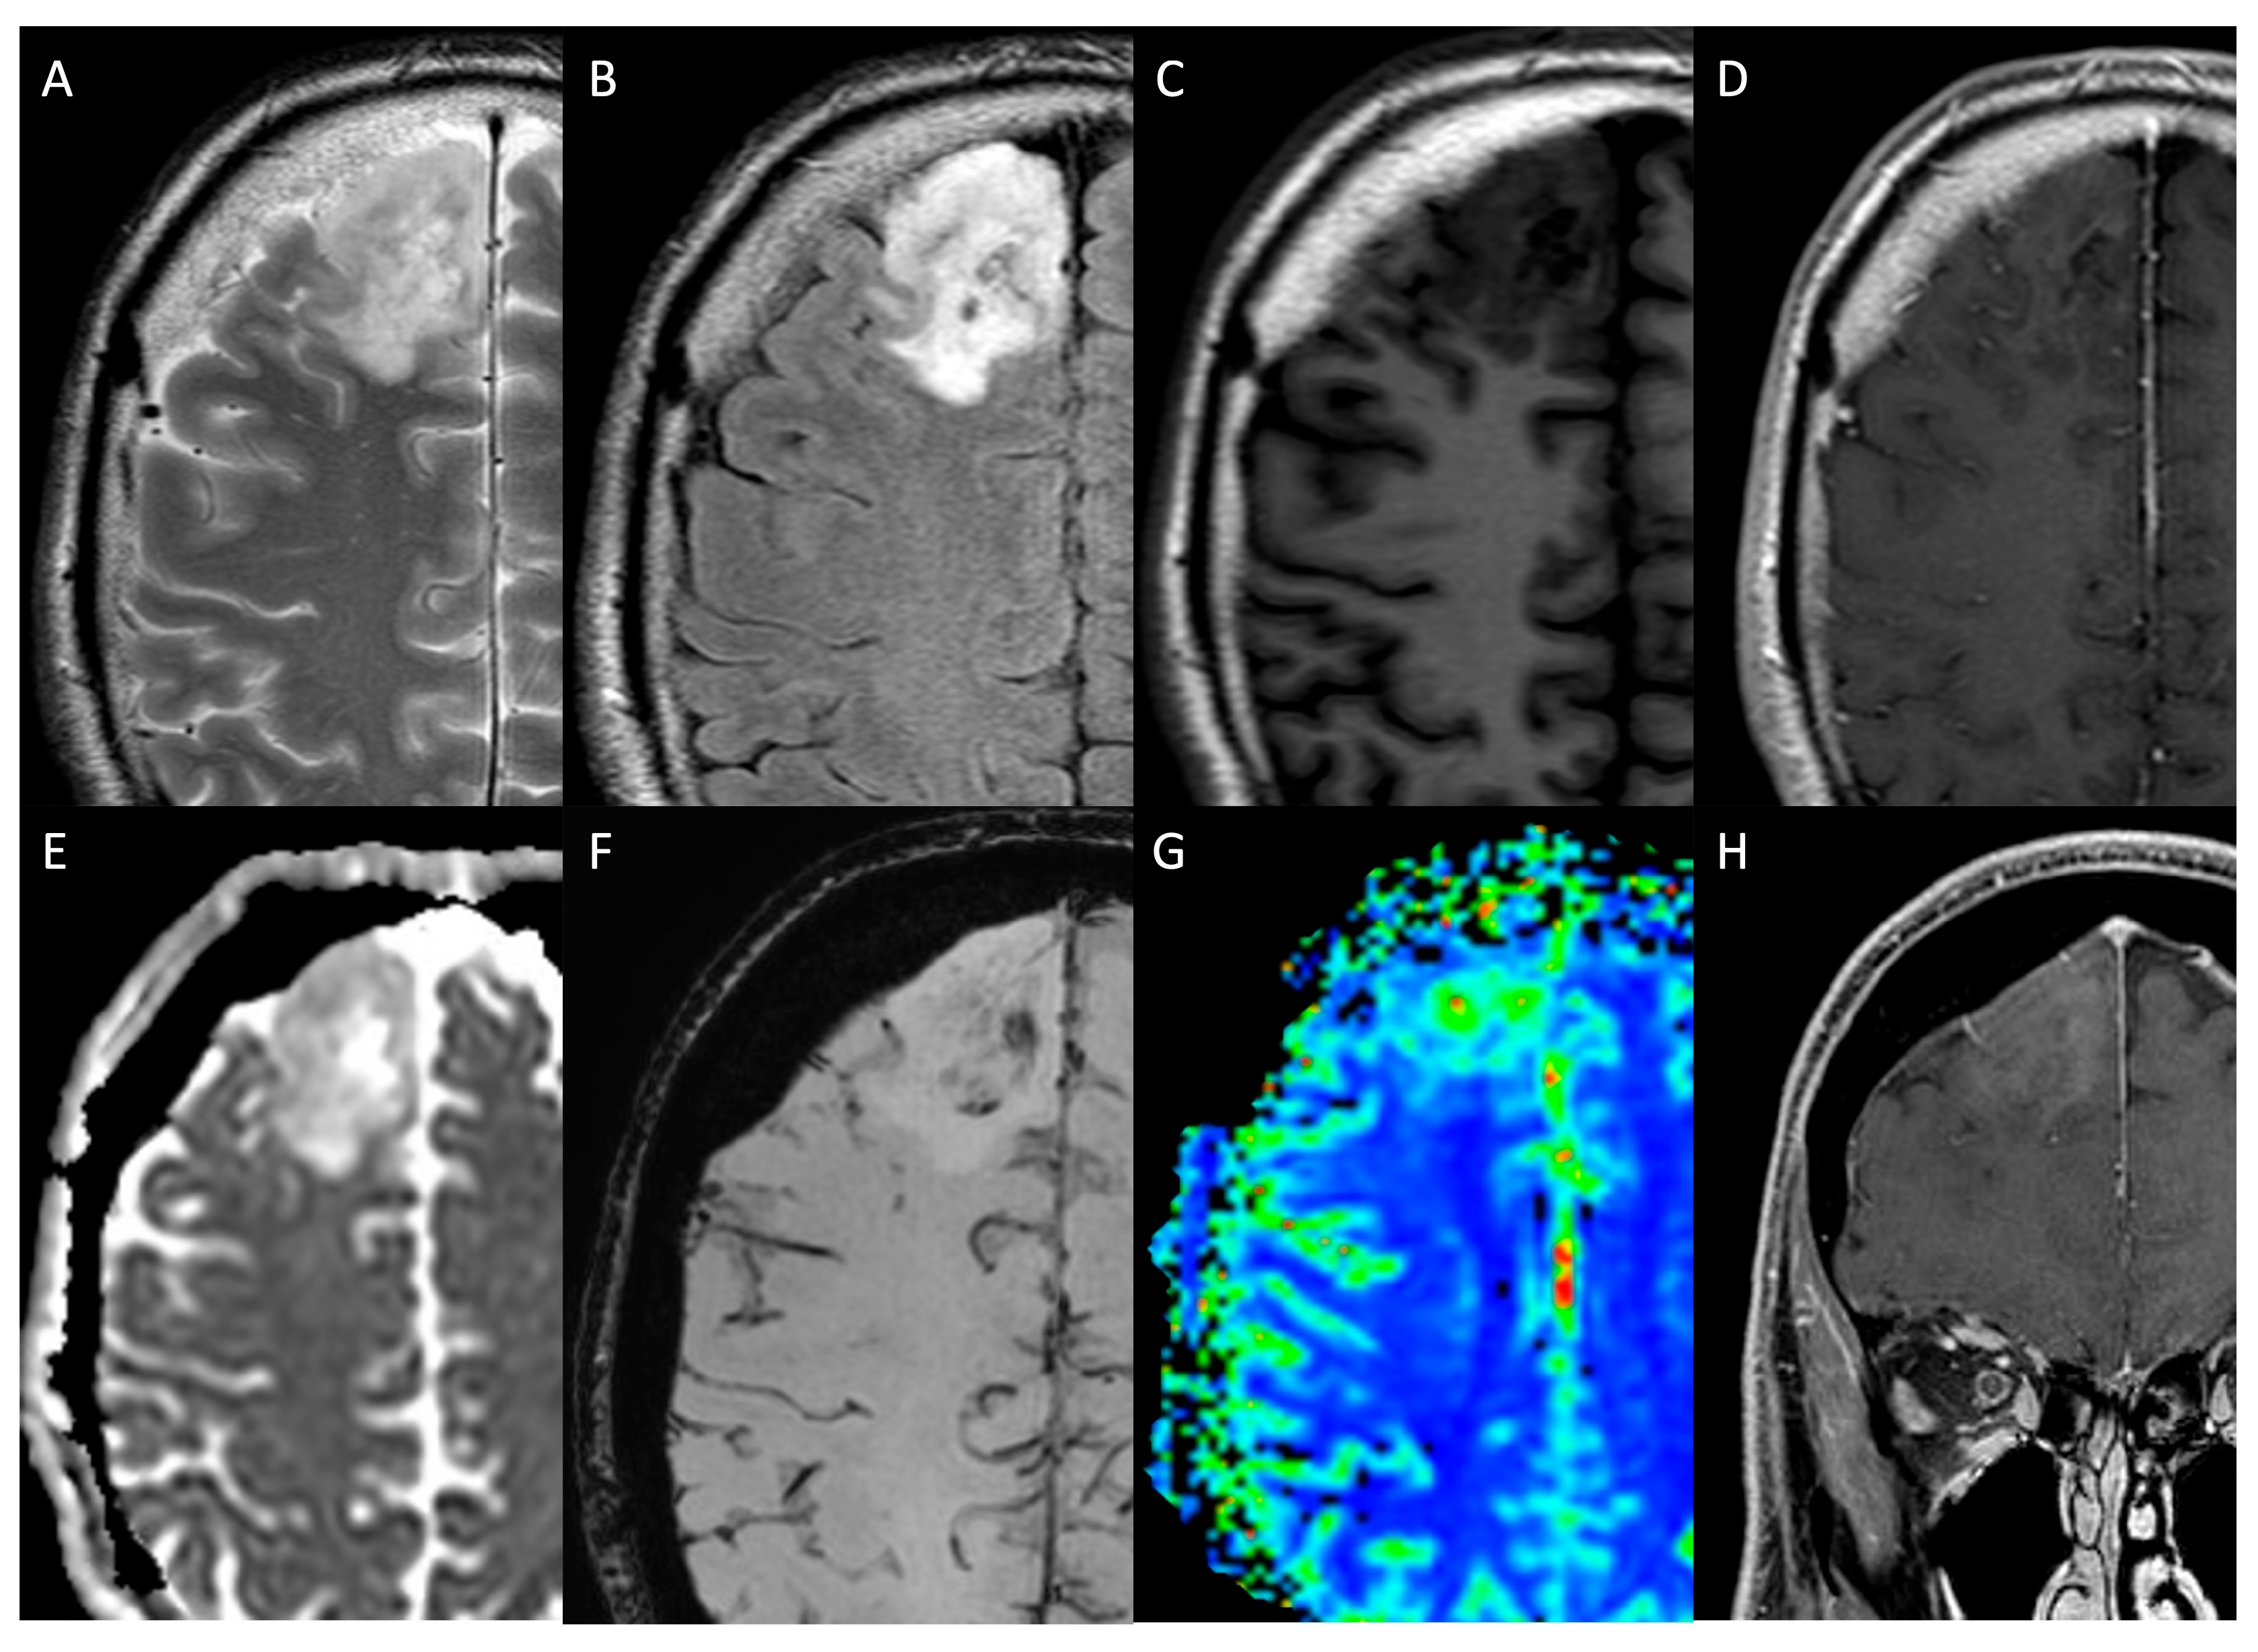

- Leclercq, D.; Delmaire, C.; de Champfleur, N.M.; Chiras, J.; Lehéricy, S. Diffusion Tractography: Methods, Validation and Applications in Patients with Neurosurgical Lesions. Neurosurg. Clin. N. Am. 2011, 22, 253–268, ix. [Google Scholar] [CrossRef]

- Sollmann, N.; Kelm, A.; Ille, S.; Schröder, A.; Zimmer, C.; Ringel, F.; Meyer, B.; Krieg, S.M. Setup Presentation and Clinical Outcome Analysis of Treating Highly Language-Eloquent Gliomas via Preoperative Navigated Transcranial Magnetic Stimulation and Tractography. Neurosurg. Focus. 2018, 44, E2. [Google Scholar] [CrossRef]

- Essayed, W.I.; Zhang, F.; Unadkat, P.; Cosgrove, G.R.; Golby, A.J.; O’Donnell, L.J. White Matter Tractography for Neurosurgical Planning: A Topography-Based Review of the Current State of the Art. Neuroimage Clin. 2017, 15, 659–672. [Google Scholar] [CrossRef] [PubMed]

- Meyer, E.J.; Gaggl, W.; Gilloon, B.; Swan, B.; Greenstein, M.; Voss, J.; Hussain, N.; Holdsworth, R.L.; Nair, V.A.; Meyerand, M.E.; et al. The Impact of Intracranial Tumor Proximity to White Matter Tracts on Morbidity and Mortality: A Retrospective Diffusion Tensor Imaging Study. Neurosurgery 2017, 80, 193–200. [Google Scholar] [CrossRef] [PubMed]

- Altabella, L.; Broggi, S.; Mangili, P.; Conte, G.M.; Pieri, V.; Iadanza, A.; Del Vecchio, A.; Anzalone, N.; di Muzio, N.; Calandrino, R.; et al. Integration of Diffusion Magnetic Resonance Tractography into Tomotherapy Radiation Treatment Planning for High-Grade Gliomas. Phys. Med. 2018, 55, 127–134. [Google Scholar] [CrossRef]

- Ius, T.; Somma, T.; Baiano, C.; Guarracino, I.; Pauletto, G.; Nilo, A.; Maieron, M.; Palese, F.; Skrap, M.; Tomasino, B. Risk Assessment by Pre-Surgical Tractography in Left Hemisphere Low-Grade Gliomas. Front. Neurol. 2021, 12, 648432. [Google Scholar] [CrossRef]

- Jiang, L.; Xiao, C.-Y.; Xu, Q.; Sun, J.; Chen, H.; Chen, Y.-C.; Yin, X. Analysis of DTI-Derived Tensor Metrics in Differential Diagnosis between Low-Grade and High-Grade Gliomas. Front. Aging Neurosci. 2017, 9, 271. [Google Scholar] [CrossRef]

- El-Serougy, L.; Abdel Razek, A.A.K.; Ezzat, A.; Eldawoody, H.; El-Morsy, A. Assessment of Diffusion Tensor Imaging Metrics in Differentiating Low-Grade from High-Grade Gliomas. Neuroradiol. J. 2016, 29, 400–407. [Google Scholar] [CrossRef] [PubMed]